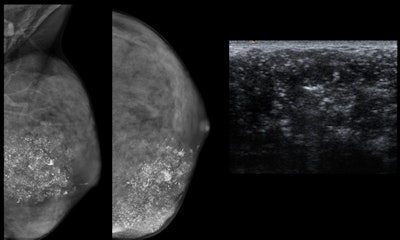

- Mammograms should be performed only in patients with lesions not completely clarified by ultrasound as a complementary technique depending on initial findings and the degree of suspicion.

- Biopsy should be avoided unless necessary. It should be performed only in suspicious, large, or enlarging masses.